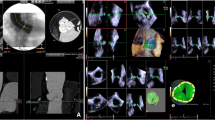

The aortic root is the direct continuation of the LVOT, beginning from the insertion of the aortic valvular cusps to the level of the sinotubular junction [4]. Its anatomy and diameter vary in patients with AS or aortic regurgitation as well as in the healthy population [17]. The measurement of the aortic annulus is the key measurement for the preparation of patients undergoing TAVI. Undersizing may lead to prosthesis migration or paravalvular regurgitation [18]. Even oversizing may cause problems such as complications related to vascular access, due to the delivery system or insufficient expansion of the prosthesis, reducing the valve’s durability [4]. We have previously described a method for the rapid, detailed 3D measurement of the aortic annulus using the ability of 3D measurements to identify the accurate diameter [19]. The aortic annulus should typically be measured in systole between the insertion of the AV cusps, not including the calcification of the aortic cusps (Fig. 1) [19, 20••]. Particularly when the annulus diameter is in the borderline range, the use of RT3D-TEE with analysis of volumetric data is helpful.

Measurement of the aortic root by RT3D-TEE. From a live 3D zoom dataset, two orthogonal long-axis views of the aortic valve were positioned in the multiplanar reconstruction mode (a sagittal, b coronal). Using a third plane, the cross-sectional view of the aortic valve for correct tracing of the aortic valve area was selected (c). The aortic valve area was traced at the moment of maximal systolic opening. Then the short-axis view was shifted to the level of the aortic annulus, where the annular area and maximum and minimal diameters were measured (d). Finally, by adjusting the imaging plane within the long-axis view, the distance between the aortic annulus and coronary ostia could be measured (e, f RCA; g, h LCA)

2D-TTE, 2D-TEE, and RT3D-TEE echocardiography were performed using a commercial ultrasound imaging system (iE33; Philips Medical Systems, Andover, MA) with 2D matrix S5-1 and a 3D matrix-array transesophageal transducer (X7-2 t). The examination protocol was as previously described [19] and is further documented in Fig. 1.

Real-time 3D Transesophageal Echocardiography

Loops were viewed after acquisition to ensure that the live 3D zoom data included LVOT and AV measurements. These full-volume DICOM loops were analyzed using QLAB. First, the orientation of an imaging plane within the 3D full volume was manipulated to gain an LVOT plane aligned parallel and about 0.5–1.0 cm below the AV. Planimetry was then performed by tracing the outline of the LVOT. Second, in multiplanar reconstruction mode, two orthogonal long-axis views of the AV and ascending aorta were selected; then a third plane perpendicular to the long-axis view was moved to the smallest AV orifice area at the moment of maximal aortic valve opening. Subsequently, the annulus was then measureed by shifting the short-axis to show the aortic annulus, where the minimum and maximum diameters and annulus area were measured. The correct level of the aortic annulus was defined as the lowest plane of the valve hinge-point (inferior virtual basal ring) [4]. In addition, as a third step, in an end-diastolic frame using two different imaging planes, the distances from the ostia of the left and right coronary arteries (LCA and RCA) to the annulus were measured. The measurement procedures are illustrated in Fig. 1.